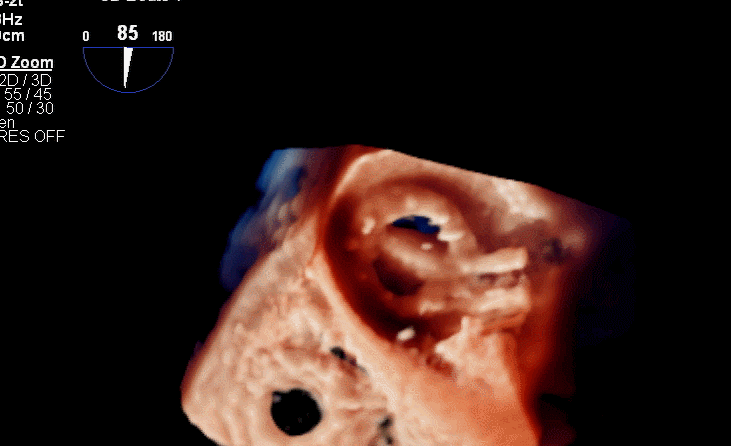

术后三维超声同时显示MV机械瓣及新的TV生物瓣